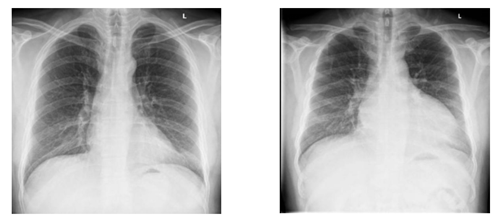

正常的心影                                                    扩大的心影